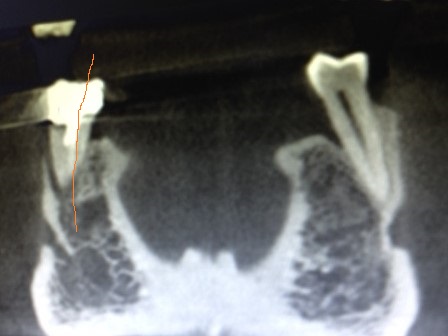

Sur le cliché si dessus l’image osseuse indique bien le fragment fracturé que je précise ci dessous avec un trait rouge:

Voici la photo de la dent extraite après mon diagnostic, et on peut constater que la dent est fracturée exactement comme je l’ai indiqué: